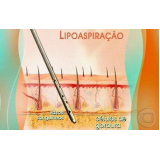

Lipoaspiração a Laser

Você merece a qualidade e comprometimento entregues pela equipe deste consultório médico e se neste momento está à procura de uma equipe que realize lipoaspiração a laser saiba que a FF Cirurgia Plástica disponibiliza de imediato este serviço para você!

Lipoaspiração a laser: atendimento eficiente e com qualidade que você sempre buscou!

Neste consultório médico você encontrará profissionais eficientes e com experiência de excelência. Usufrua de bom atendimento, através dos melhores preços do mercado e de assistência especializada sempre à sua disposição! Leve as suas dúvidas, converse com a equipe da FF Cirurgia Plástica. Contrate bons serviços e sinta-se mais seguro para cuidar da saúde.